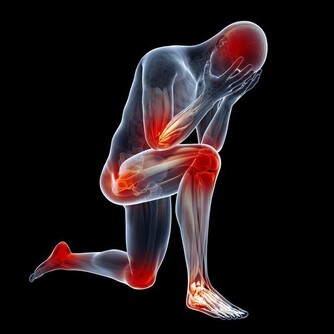

中醫理論認為: 氣血不通暢,則會疼痛。而其主要有兩個原因,一是老人年本身體虛,自身調節能力較弱,再加如果受了風寒,氣血則會更不通暢。如果不及時調整,氣血不通之後,隨之而來的比如心臟病、等各種器質性的病變。

以下圖片來源 西醫認為: 缺鈣和脊椎的形變是最大的禍首。如果不及時治療,那麼,隨著鈣質的繼續流失、包括頸椎和腰椎兩大人體主要部位的形變,隨之而來的由骨折引起的死亡,腰椎、頸椎引起的腦供血不足和癱瘓等等,也會慢慢接近。